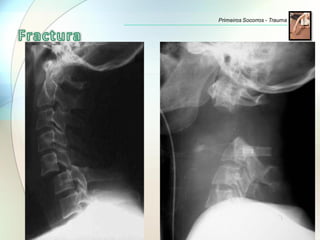

Estando a dor intensa no local e inchaço

presentes em ambas as situações, as fracturas

diferenciam-se das entorses por:

• Falta de força.

• Perda total ou parcial dos movimentos.

• Encurtamento ou deformação do membro

lesionado.